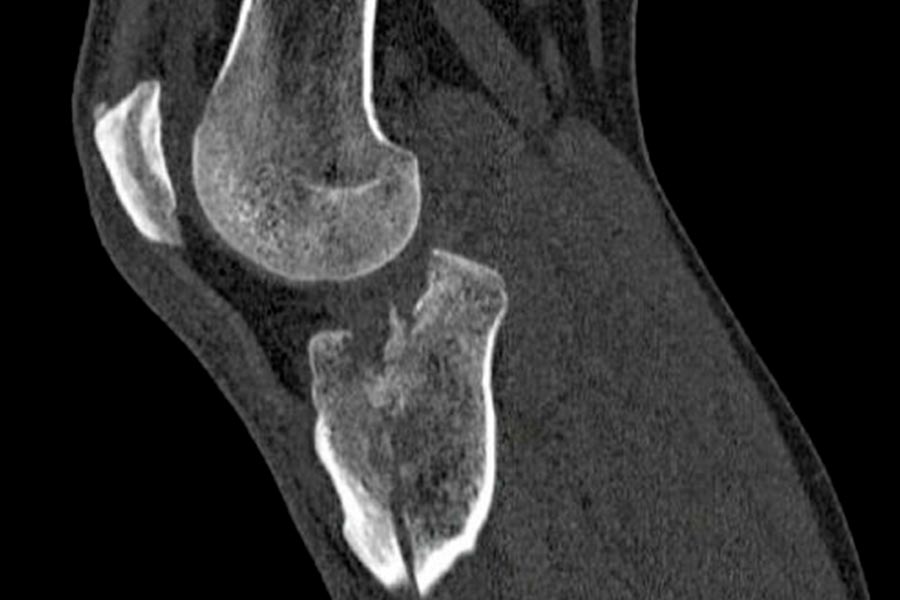

Varón 36 años. Sufre traumatismo directo en pierna derecha con mecanismo de hiperextensión durante la disputa de un balón jugando al fútbol.